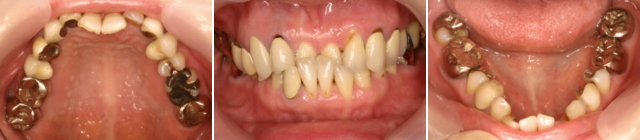

口腔内を診てみますと虫歯ではなく、噛み合わせの関係で奥歯に歯を揺さぶる悪い力がかかり、支えている骨にダメージを与えて歯周病を悪化させていました。まず先日書きました初期治療を行い、症状を安定させたのですが、歯にかかる悪い力はコントロール出来ませんでした。噛みあわせの治療のために、矯正治療が必要なことを話し理解していだだき、治療を開始しました。 仕事もされているため治療期間を短くしてほしいとの希望もありました。

専門的には、「反対咬合」と呼んでいます。また、上下の歯列はV字型になり、特に下顎の小臼歯は内側に倒れています。今までの矯正治療では歯を水平的に動かすことをしていますが、このようなケースは上下の噛み合わせの高さが低いために機能的に反対咬合となってしまっています。そのため、積極的に高さをあげる必要があります。その時に威力を発揮しますのがマルチループというテクニックです。通常2~3年かかる治療が1年2が月で終わりました。患者さんは 結果にとても喜んでいます。その後、問題がある奥の銀歯の歯の治療をすることとなりました。マルチループのテクニックは、ワイヤー(針金のようなもの)をベンドする(曲げる)のがたいへんですが、こんなに短期間で理想とするゴールにいける素晴らしいテクニックと感じています。